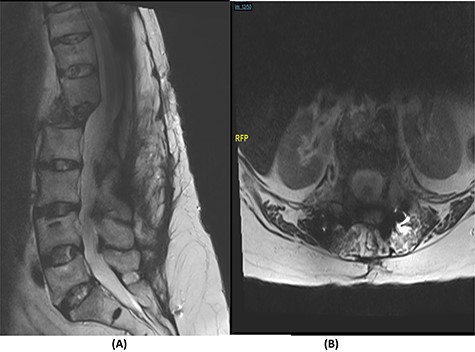

Fourteen months later, the patient presented to the ED complaining of generalized body pain associated with malaise. The neurological examination was unremarkable. An MRI of the lumbar spine showed recurrence of the lesion with loosening and pullout of the implant, kyphosis and dislocation, with cord compression and collection (Fig. 2). Computed tomography (CT) scan showed a burst fracture of the L1 vertebra with loose screws (Fig. 3). CRP was 21 mg/l, ESR was 115 mm/h and procalcitonin was 0.051 ng/ml. The decision was made to do a CT-guided biopsy from the left paraspinal mass of T12–L1. The tissue biopsy was subjected to TB-polymerase chain reaction testing and acid-fast bacillus culture; both results were positive for M. tuberculosis. The patient was diagnosed with TB spondylitis and was started on the full anti-TB four-drug regimen.

(A) Sagittal spine CT demonstrating a burst fracture involving L1 vertebral body with retropulsion of fragments and epidural soft tissue mass indenting the conus medullaris at the level of T12–L1. (B) Axial spine CT of the corresponding level of L2 vertebral body. (C) Axial spine CT of the corresponding level of L3 vertebral body. (D) Axial spine CT of the corresponding level of T11 vertebral body.